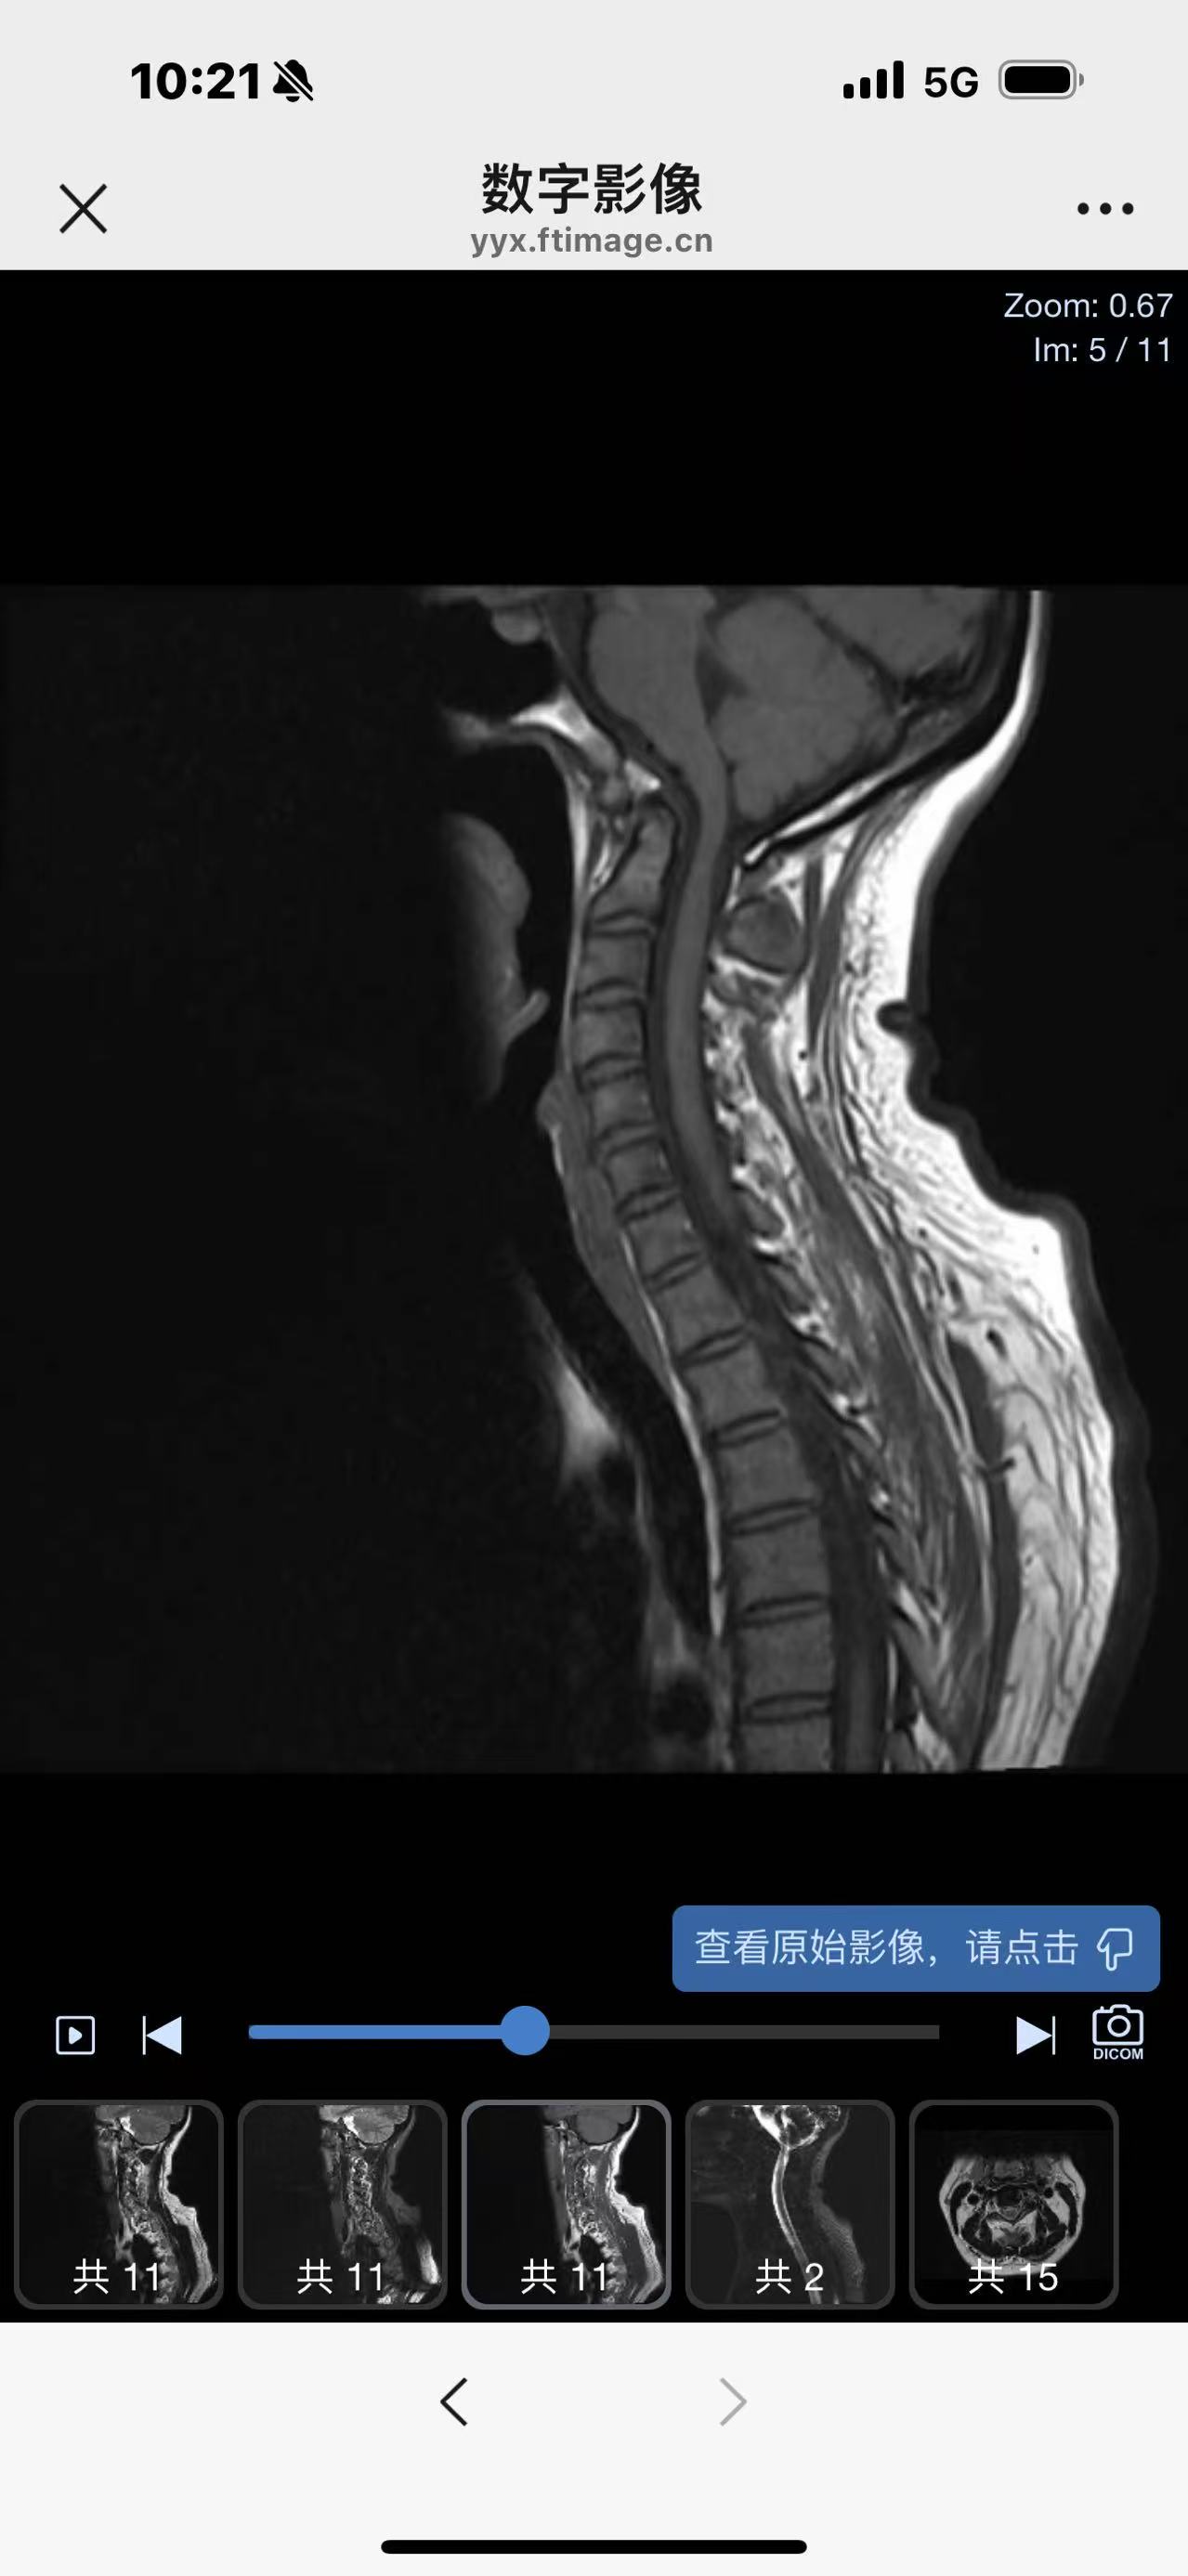

• 诊断:寰枢椎脱位

• 影像:

• 术后影像: